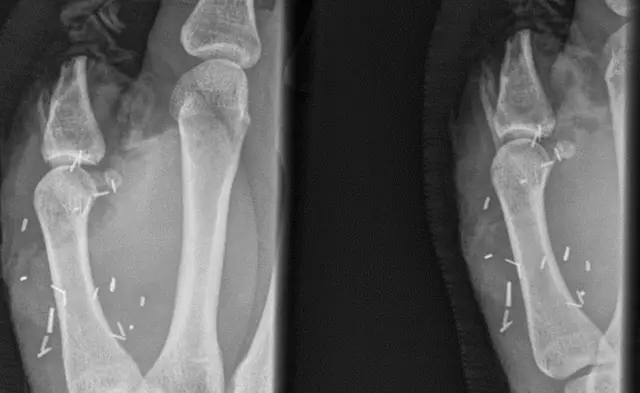

Австралієць Зак Мітчел пересадив великий палець ноги на руку. Хірургічна операція мала на меті замінити великий палець руки чоловіка, який він втратив через травму на тваринницькій фермі.

У квітні його травмував бик - руку затисло об паркан.

Перед цим хірурги двічі пробували пришити назад його великий палець руки, однак операції були невдалими.

Операція тривала вісім годин.

Операцію провели у Sydney Eye Hospital. Там відзначають, що на пересадку цілого великого пальця ноги йдуть досить рідко, тоді як трансплантація частин пальців трапляється частіше.